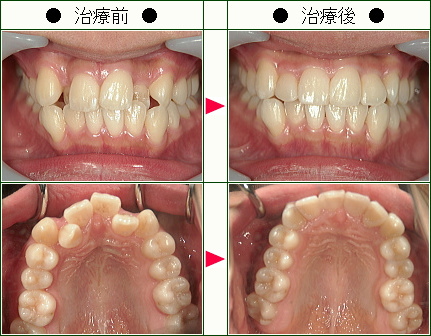

歯のデコボコ矯正の治療症例解説<上だけの症例>(19歳以下)--部分矯正--その4

☆歯のデコボコ矯正症例[C.H様 18歳 女性]